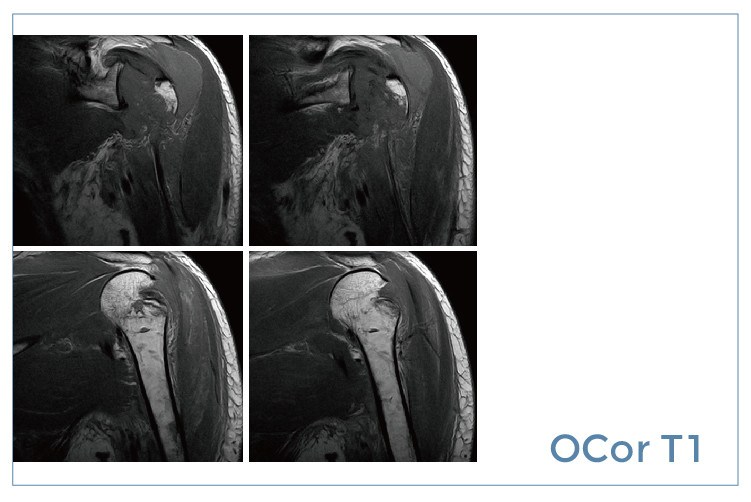

【朗润影像档案】20190830磁共振影像病例结果讨论